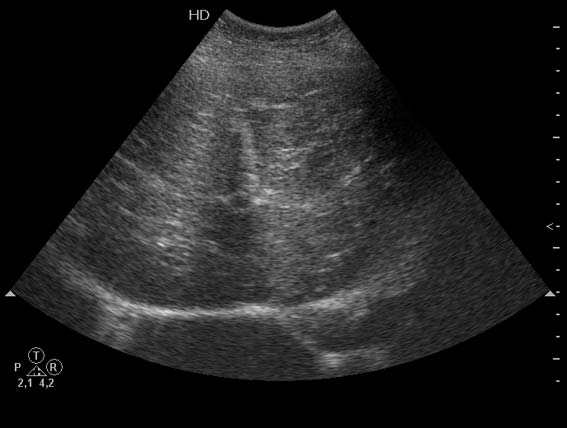

Женщина 82 лет с болями в эпигастральной области.

Очаги были пропущены при ультразвуковом исследовании.

Потому что при повторном УЗ-исследовании (уже после КТ) они были обнаружены.Serg писал(а):Почему Вы пишете, что очаги пропущены?

И потому что так считают хирурги, которые уверены, что на УЗИ видно всё.